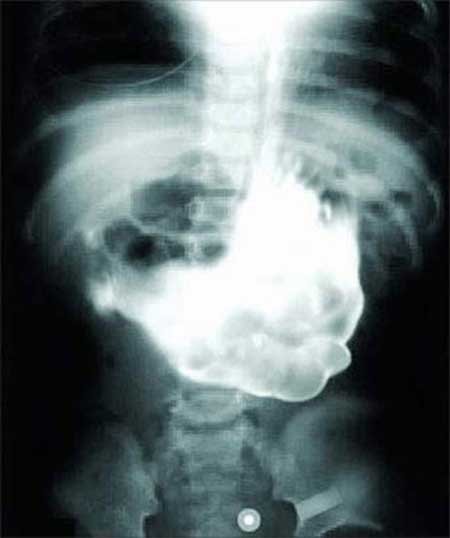

Dù các bác sĩ cho rằng ông Ron Sveden, 75 tuổi, đang bị một khối u ung thư

phát triển ở phổi trái, thì thực tế họ lại tìm thấy một cây đậu Hà Lan đang mọc

trong đó.

Người đàn ông Nga này phải trải qua một cuộc phẫu thuật để lấy đi một khối ung thư đang phát triển song các bác sĩ phát hiện thấy một cây thông nhỏ đang mọc trong phổi của anh chàng.